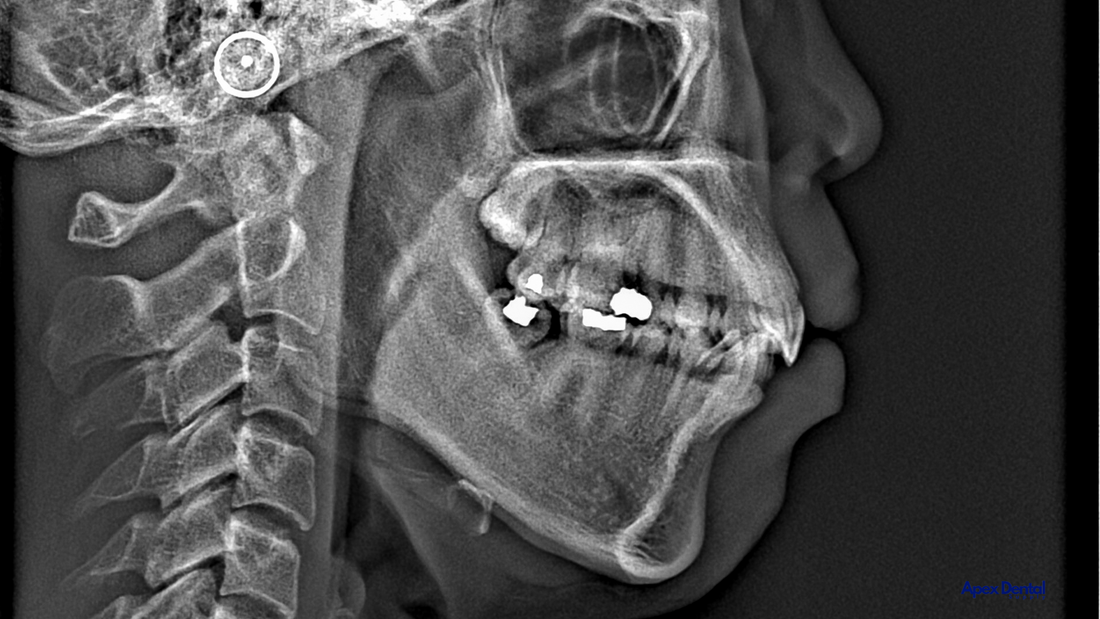

The Role of CBCT in Early Orthodontic Diagnosis

CBCT has revolutionized orthodontic imaging by providing three-dimensional (3D) visualization of craniofacial structures. Unlike conventional two-dimensional radiographs, CBCT allows practitioners to assess:

Airway volume and dimensions: Identifying airway constrictions or obstructions.

Skeletal morphology: Evaluating maxillary and mandibular development.

Nasal and sinus abnormalities: Detecting deviations or blockages that may affect breathing.

Tongue space and posture: Understanding tongue placement and its impact on airway patency.

Several studies underscore the significance of CBCT in diagnosing airway issues. A study by El and Palomo (2010) demonstrated a correlation between reduced airway volume and Class II skeletal patterns, highlighting the importance of early intervention.